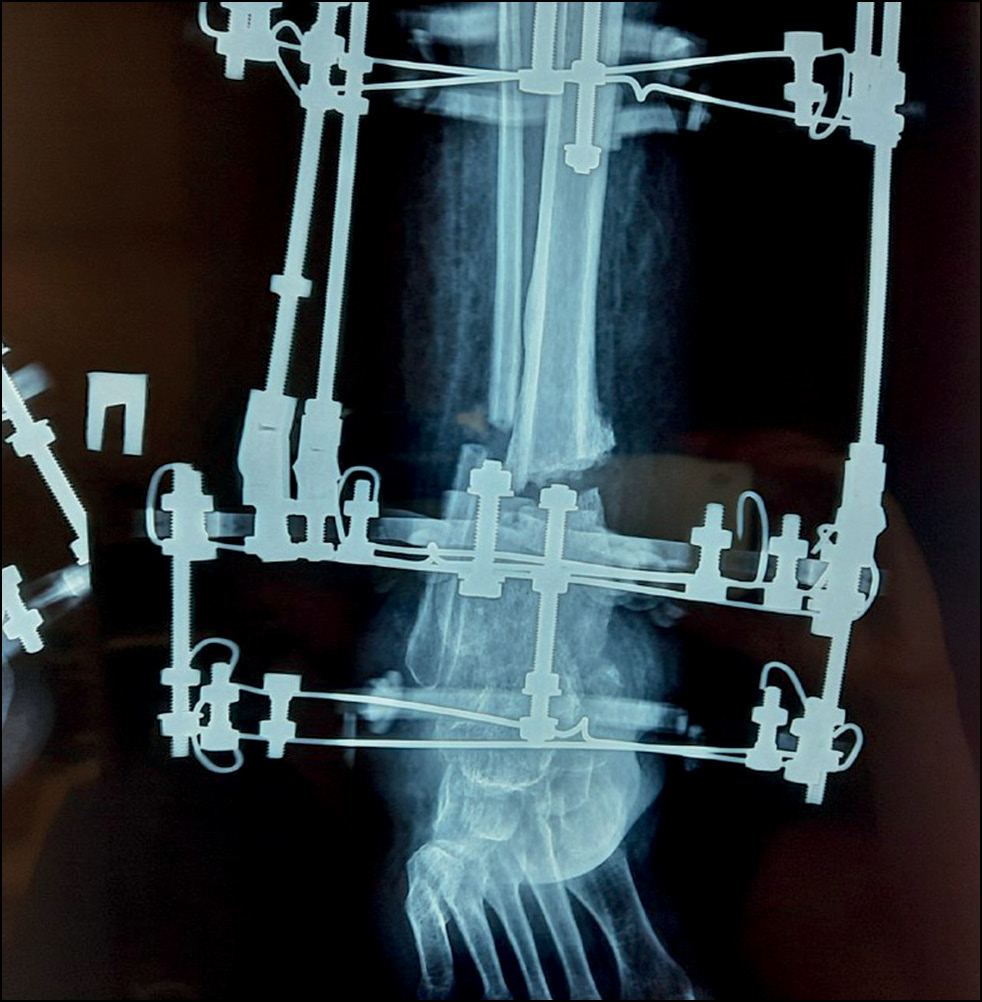

Через 10 дней после операции начата этапная дозированная дистракция в зоне остеотомии на переднезадних стержнях, соответствующих оси большеберцовой кости, 0,75 мм/сут, на медиальном стержне — 1,0 мм/сут. Каждые 2 недели проводилось рентгенографическое исследование для оценки степени коррекции деформации и контроля удлинения. После коррекции углового смещения (рис. 9) скорость дистракции на трёх стержнях была одинаковой — 0,75 мм/сут. Через 8 недель после начала дистракции, когда диастаз между костными фрагментами составлял 40 мм, была достигнута компенсация укорочения и деформации конечности, дистракция была остановлена. К этому времени отмечались начальные признаки формирования костного регенерата, рентгенологические признаки снижения МПКТ оставались на прежнем уровне. Маркеры костного метаболизма не выходили за пределы референса — остеокальцин 34,76 нг/мл (11–43), С-концевой телопептид коллагена I типа — 0,346 нг/мл (0,3–0,57). После коррекции дефицита витамина D (приём колекальциферола 50 000 МЕ еженедельно в течение 8 недель внутрь, далее 2000 МЕ ежедневно внутрь) уровень ПТГ нормализовался и составил 61,7 пг/мл (15–65).

В последующем рентген-контроль осуществлялся ежемесячно. Плотность костного регенерата увеличивалась, однако отмечалась отрицательная динамика МПКТ. Через 4 месяца после операции обнаружены признаки гипотрофии регенерата — его сужение и извитая линия пониженной плотности, расположенная поперечно, ограниченная зоной с повышенной плотностью костной ткани (склероз) на уровне средней части регенерата; это также сопровождалось общими признаками сниженной МПКТ (рис. 10).

Рис. 10. Рентгенограмма в косой проекции с признаками гипотрофии регенерата.

Fig. 10. X-ray image in oblique projection with signs of regenerate malnutrition.

В связи с формированием гипотрофии регенерата на фоне стандартного лечения принято решение о добавлении к терапии терипаратида 20 мкг в день подкожно, длительность лечения составила 6 месяцев. Терипаратид — рекомбинантный человеческий паратиреоидный гормон, который является активным фрагментом эндогенного человеческого паратгормона и физиологическое действие которого заключается в стимуляции формирования костной ткани посредством прямого влияния на остеобласты. Несмотря на риск развития осложнений, связанных со сниженной устойчивостью к механическому воздействию на ткани (как следствие нейропатии), и нагноения, разрешена дозированная нагрузка не более 25% от массы тела.

Рис. 11. Рентгенограммы после демонтажа аппарата Илизарова.

Fig. 11. X-ray images after dismantling of Ilizarov device.

Через 4 месяца лечения терипаратидом отмечено четырёхкратное увеличение маркера костеобразования (остеокальцина) — 133,1 нг/мл (11–43). По результатам денситометрии отмечено увеличение МПКТ на 9,7% в лучевой кости и до 5% — в бедренной кости. По рентгенологическим данным выявлена положительная динамика в отношении формирования костного регенерата: увеличение плотности, однородности, снижение проявлений общего снижения МПКТ. Ещё через 2 месяца отмечалось формирование кортикальной пластинки на всём протяжении регенерата, после чего принято решение о демонтаже аппарата Илизарова, общий срок применения которого составил 10 месяцев (рис. 11).